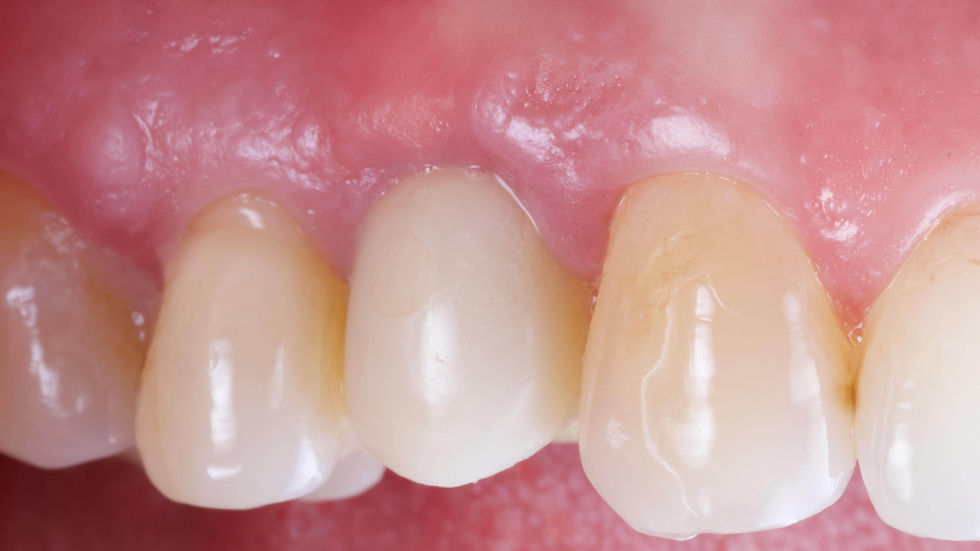

Healing at 3 months.

Tissues are healed, but still not completely mature. The membrane, not yet entirely reabsorbed, is still visible in transparency.